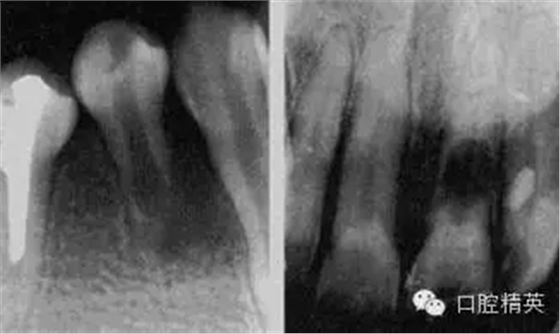

急性化膿性根尖周炎又稱急性牙槽膿腫,是由急性漿液性根尖周炎發(fā)展而來的,也可由慢性根尖周炎急性發(fā)作所致。急性化膿性根尖周炎在其發(fā)展過程中,因其膿液所在部位不同而劃分為根尖膿腫、骨膜下膿腫和黏膜下膿腫三個(gè)階段,主要癥狀為疼痛和腫脹,嚴(yán)重者伴有全身癥狀。

1.根尖膿腫 患牙有自發(fā)性、持續(xù)性、定位性劇烈跳痛,患牙浮起,咬合痛;檢查患牙叩痛、松動(dòng)明顯,根尖部牙齦潮紅,有輕度捫痛。牙髓無活力。

2.骨膜下膿腫 患牙持續(xù)性劇烈跳痛達(dá)最高峰,更覺高起、松動(dòng),觸痛劇烈,相應(yīng)頜面部軟組織腫脹、壓痛,并伴有全身癥狀;檢查患牙為重度叩痛、Ⅲ°松動(dòng),牙齦紅腫,移行溝變平,壓痛明顯,捫診有深部波動(dòng)感,牙髓無活力。

3.黏膜下膿腫 膿液已達(dá)黏膜下,疼痛減輕,全身癥狀緩解;檢查患牙叩痛(+)—(++),松動(dòng)I°,根尖區(qū)黏膜腫脹呈半球形隆起,波動(dòng)感明顯,牙髓無活力。